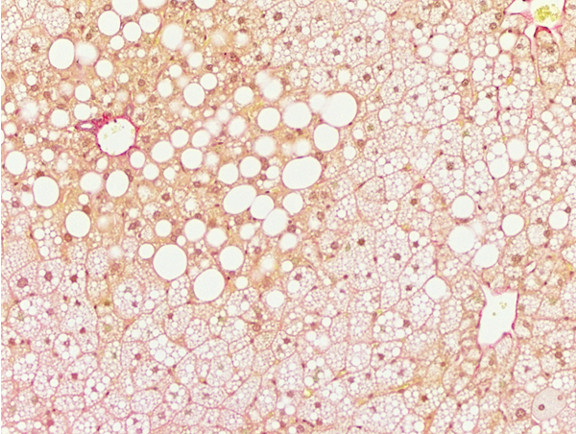

Figure 6: Histopathology for C57BL/6NTac mice placed on D09100310 diet (MASH B6NTac) or kept on chow diet (Control B6NTac) from 6 weeks of age. Animals were on diet for 27, 35 or 53 weeks. Hematoxylin and eosin (H&E) staining illustrates morphological changes including steatosis and infiltration of immune cells. Activated HSCs were identified in liver sections by using a rabbit polyclonal antibody to alpha-smooth muscle actin (a-SMA) (1:500 dilution; ab5694; Abcam, Cambridge, MA) which was detected by an anti-rabbit IgG embedded polymer with embedded horseradish peroxidase and visualized with 3,3′-diaminobenzidine (DAB) chromogen (Agilent, Carpentaria, CA). Hepatocellular lipid droplets were identified by visualization of the lipid-binding protein adipophilin known to be expressed in steatotic livers. Sections of livers were probed using a rabbit polyclonal anti-adipophilin antibody (1:200 dilution; NB110-40877, Novus Biologics, Littleton, CO) which was detected by an anti-rabbit IgG embedded polymer with embedded horseradish peroxidase and visualized with 3,3′-diaminobenzidine (DAB) chromogen (Aligent, Carpentaria, CA). Picrosirius red (PSR) staining illustrates collagen I and III fibers and is used to measure fibrosis. The same individual MASH or control animal is shown for all four stains in a particular time point. Different individual animals were used for each time point (i.e. data is not longitudinal by animal). Histopathology services provided by IDEXX BioAnalytics.